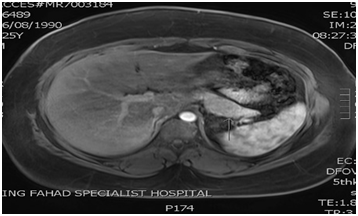

MR abdomen with contrast

Surgery team has been consulted the patient underwent successful subtotal pancreatectomy and splenectomy. Postoperatively, blood sugar started to raise, intravenous insulin infusion initiated then shifted to subcutaneous insulin (glargine with pre-meals Aspart) for few days. After 10 days, post-surgery, the patient was discharged home with stable condition without insulin nor oral medication.

Histopathology report of pancreatic surgery was: well differentiated neuroendocrine tumor, Grade2 (Figure 3). Based on this report, Molecular genetics MEN1 gene sequencing was requested. A novel mutation was identified: heterozygous c.1049+2T>A variant.

Figure 3 focal mass like lesion in the body of the pancreas with ill-defined outline (size5cm x 3.2cm).